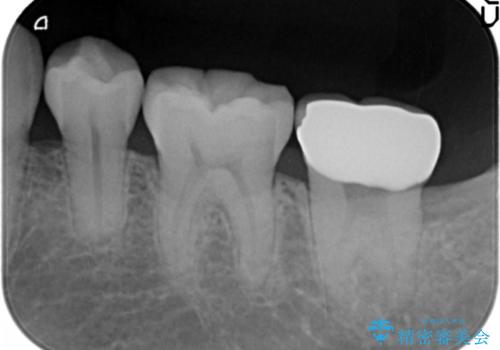

2:歯周外科手術を行う

3:2週間後に抜糸

4:歯ぐきが少し落ち着いたところで仮歯にする

5:手術から5ヶ月待って、最終形成を行う

6:歯型をとり、クラウンを作成、仮着する

7:色、形、咬みごこち等問題なければクラウンを本セットする